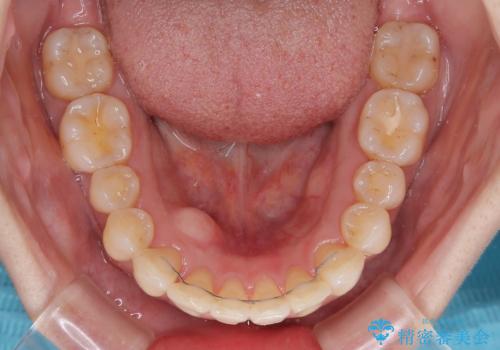

- 全体的なデコボコと、以前抜歯した歯のスペースを閉じた部分が気になるとのことで来院された患者様です。

左上第一大臼歯を抜歯した際に、スペースを閉じたそうですが、歯が傾斜してものが挟まって不快とのことでした。

インビザライン矯正で全体の歯列と整えるとともに、左上第一大臼歯部にはスペースを作り、インプラントによる補綴治療を行うこととしました。

歯の傾斜が改善され、インプラントによるクラウンが装着されたことで、物が挟まることもなくなりました。